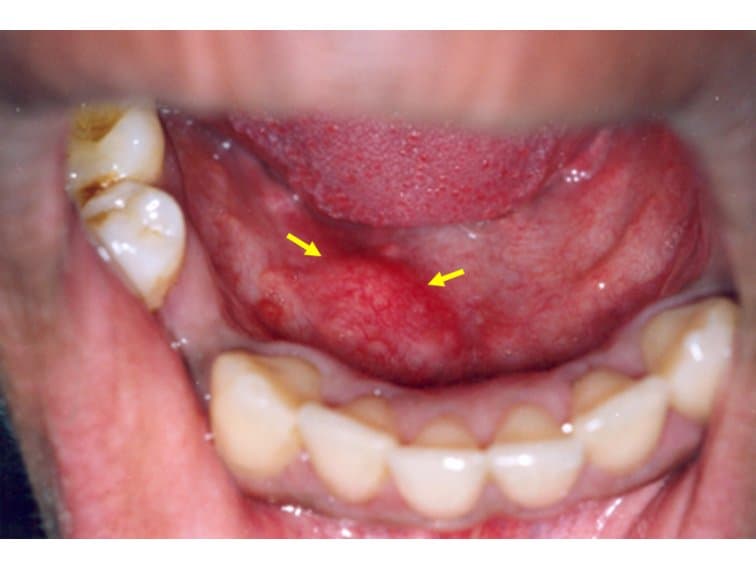

Các triệu chứng ung thư tuyến nước bọt thường bao gồm: sưng, hoặc có khối u ở khu vực phía trước tai, má, cằm, môi hoặc trong miệng; khó nuốt, tê ở mặt, vv..

Có khối u ở khu vực tai, má, miệng, vv… là triệu chứng thường gặp của ung thư tuyến nước bọt.

- Khối u (thường không đau) ở khu vực ở phía trước của tai, má, cằm, môi hoặc trong miệng